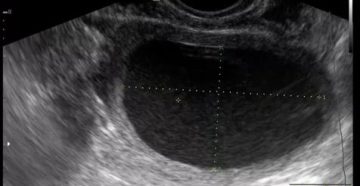

Жидкость в позадиматочном пространстве. Причины, лечение, последствия Во время проведения УЗИ малого тазау женщин может…